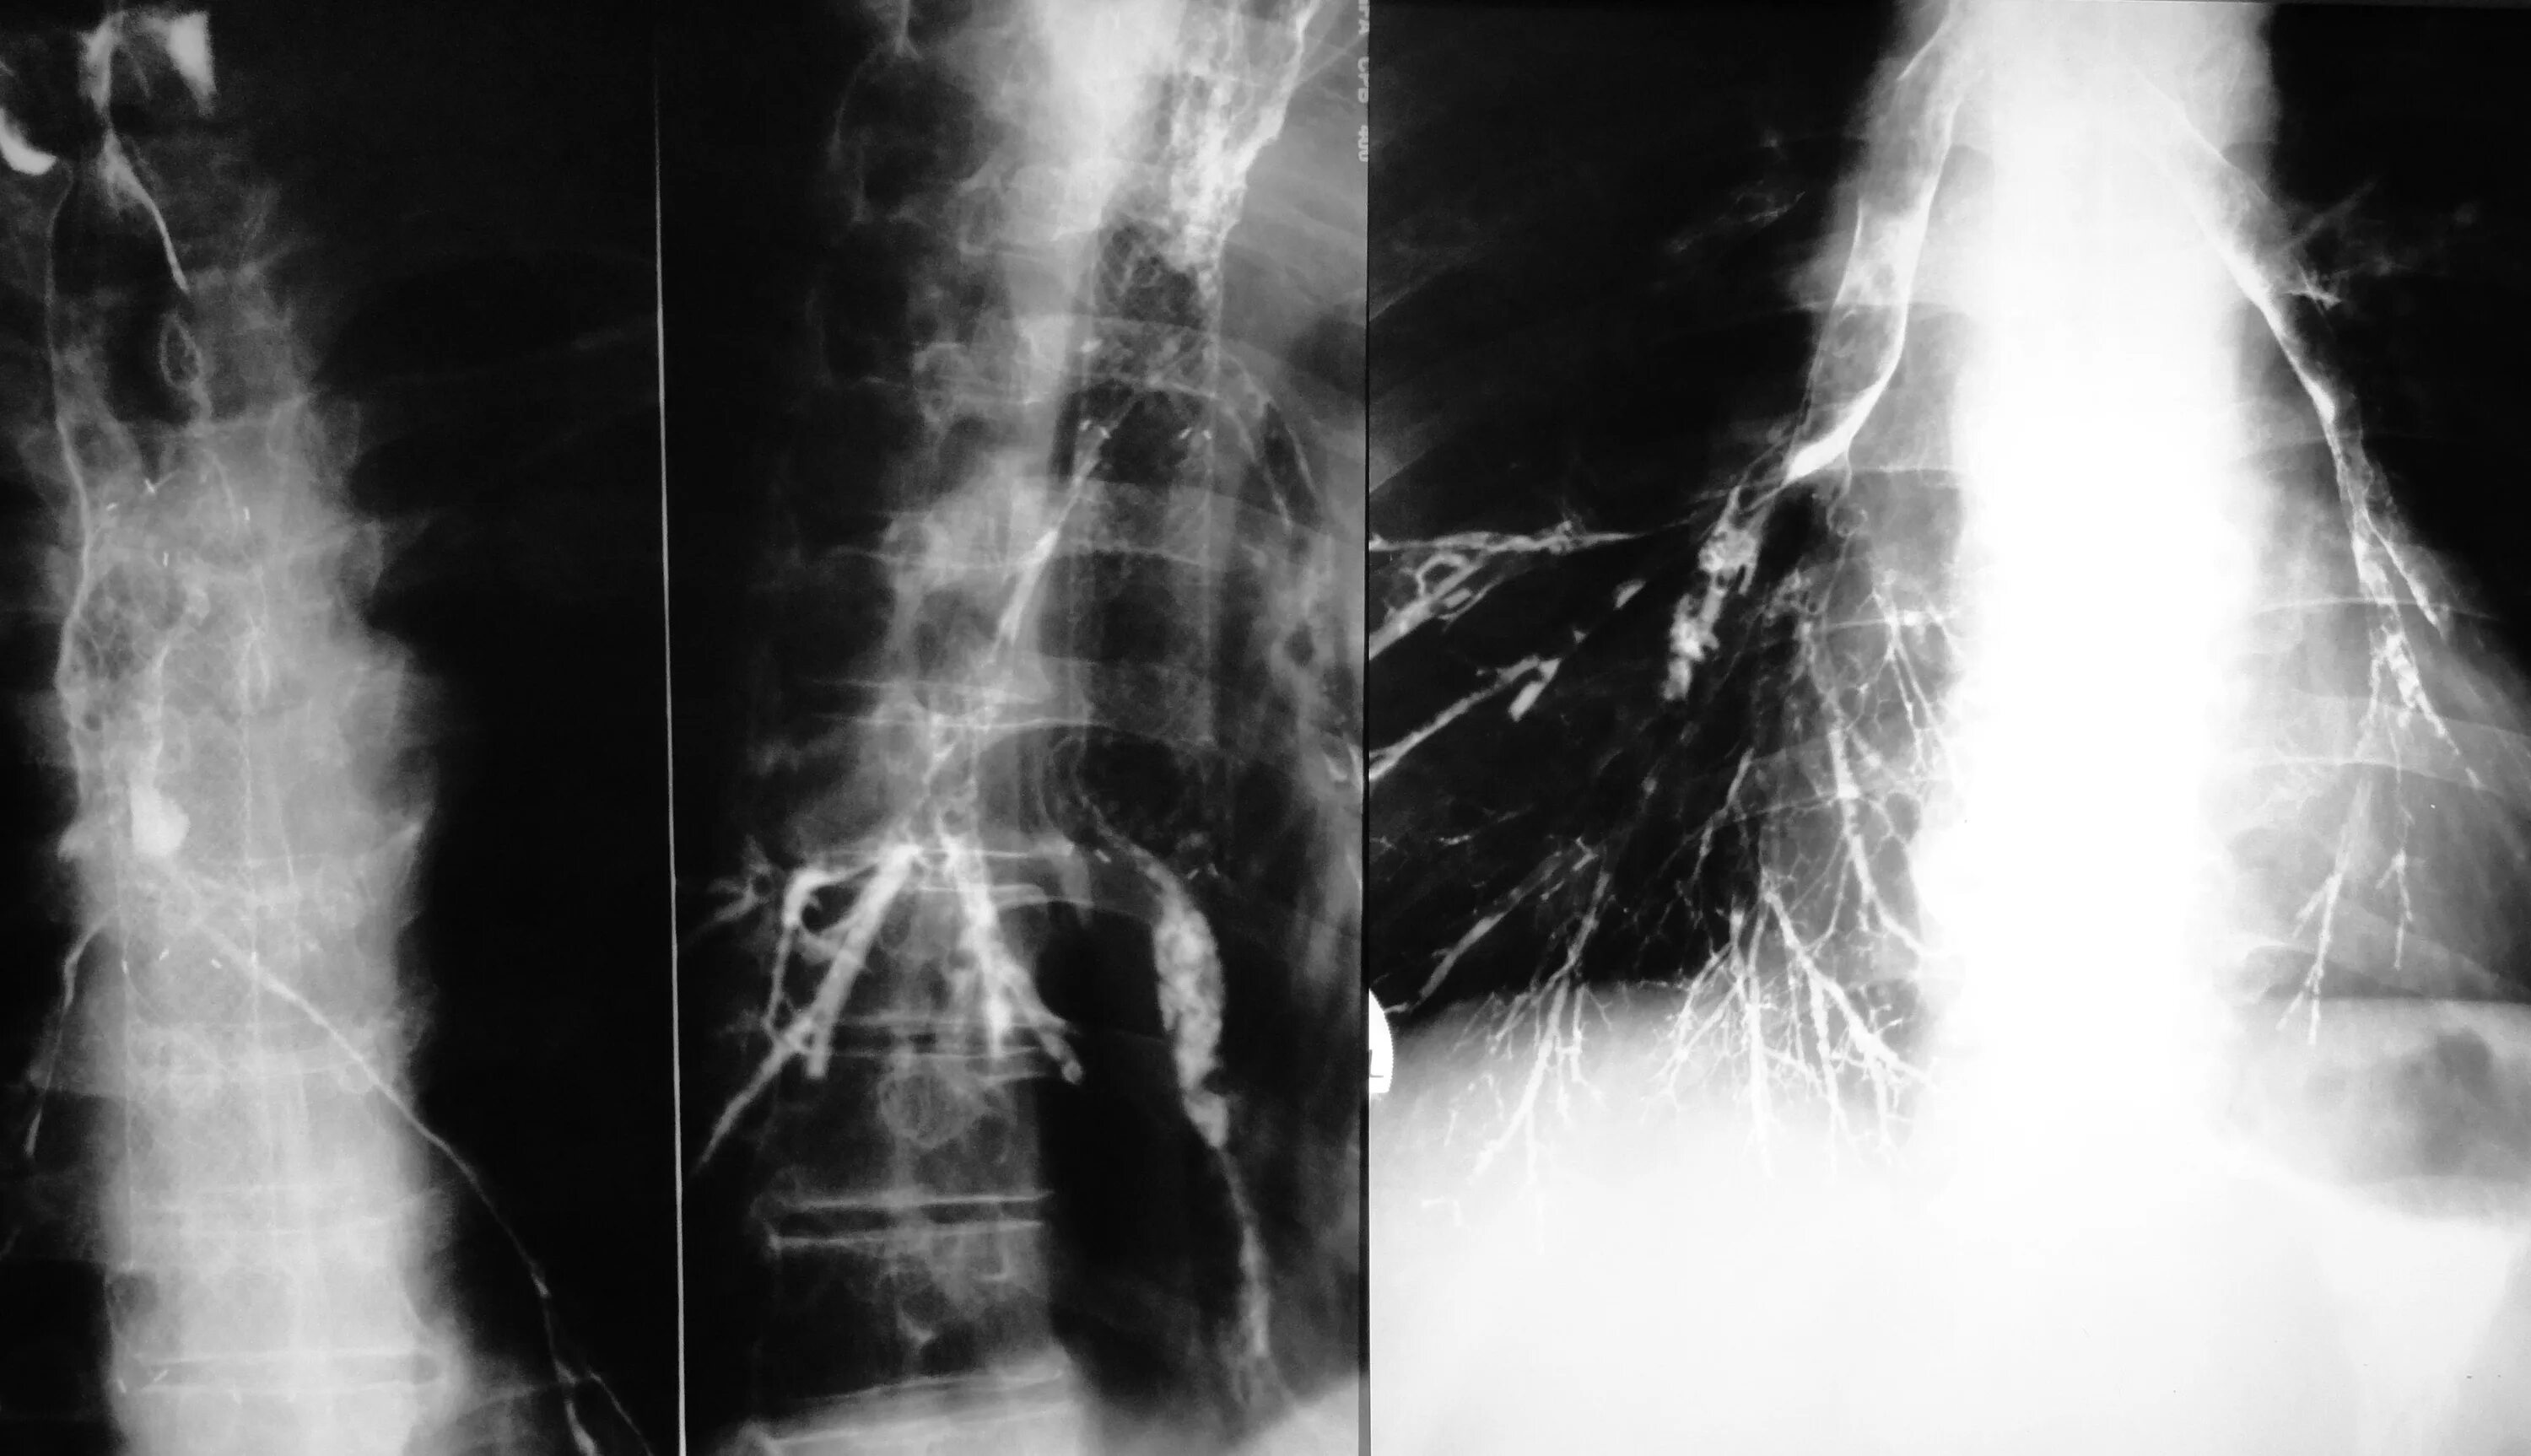

Диффузный эндобронхит